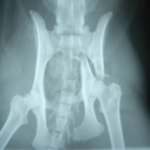

症例:交通事故による椎体脱臼

柴犬:9歳、避妊雌

交通事故直後、胸腰部に激しい疼痛、両後肢に完全麻痺を認め、シェフシェリントン徴候を呈していました。レントゲン検査において、第11-12胸椎間の脱臼が認められました。

脊髄の減圧、脊柱管の再構築・安定化を目的に、片側椎弓切除術およびMatrixMANDIBLE Plateによる椎体固定を実施しました。

隣接椎体を架橋するようにプレートを設置しました。

術後レントゲン写真